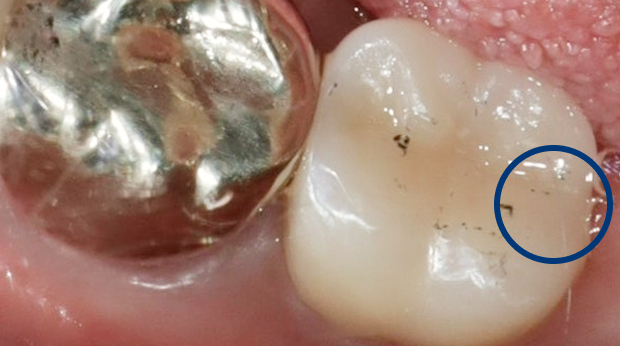

광진구에서 만나는 전문적인 장비와 진료

연세원드림치과는 전문적인 장비와 진료 시스템을 통해

안전하고 편안한 진료 환경에서

환자 맞춤형 수준 높은 진료를 진행하고 있습니다.